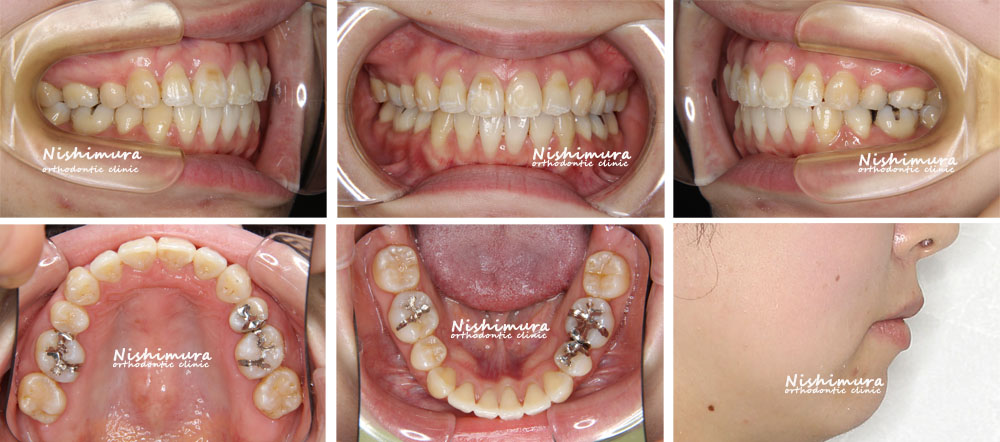

口元が出ている(口ゴボ) 症例3

上下の前歯が前に出ている気がする、口唇が閉じにくい

上下顎前突、上下顎前歯唇側傾斜、口唇閉鎖不全

33歳

マルチブラケット装置、歯科矯正用アンカースクリュー

上顎両側第一小臼歯、下顎両側第二小臼歯

2年 4ヵ月(27回)

約87万円(矯正歯科治療は公的健康保険の適用外の自費診療となります。)

治療前

治療前の写真

治療後

治療後の写真